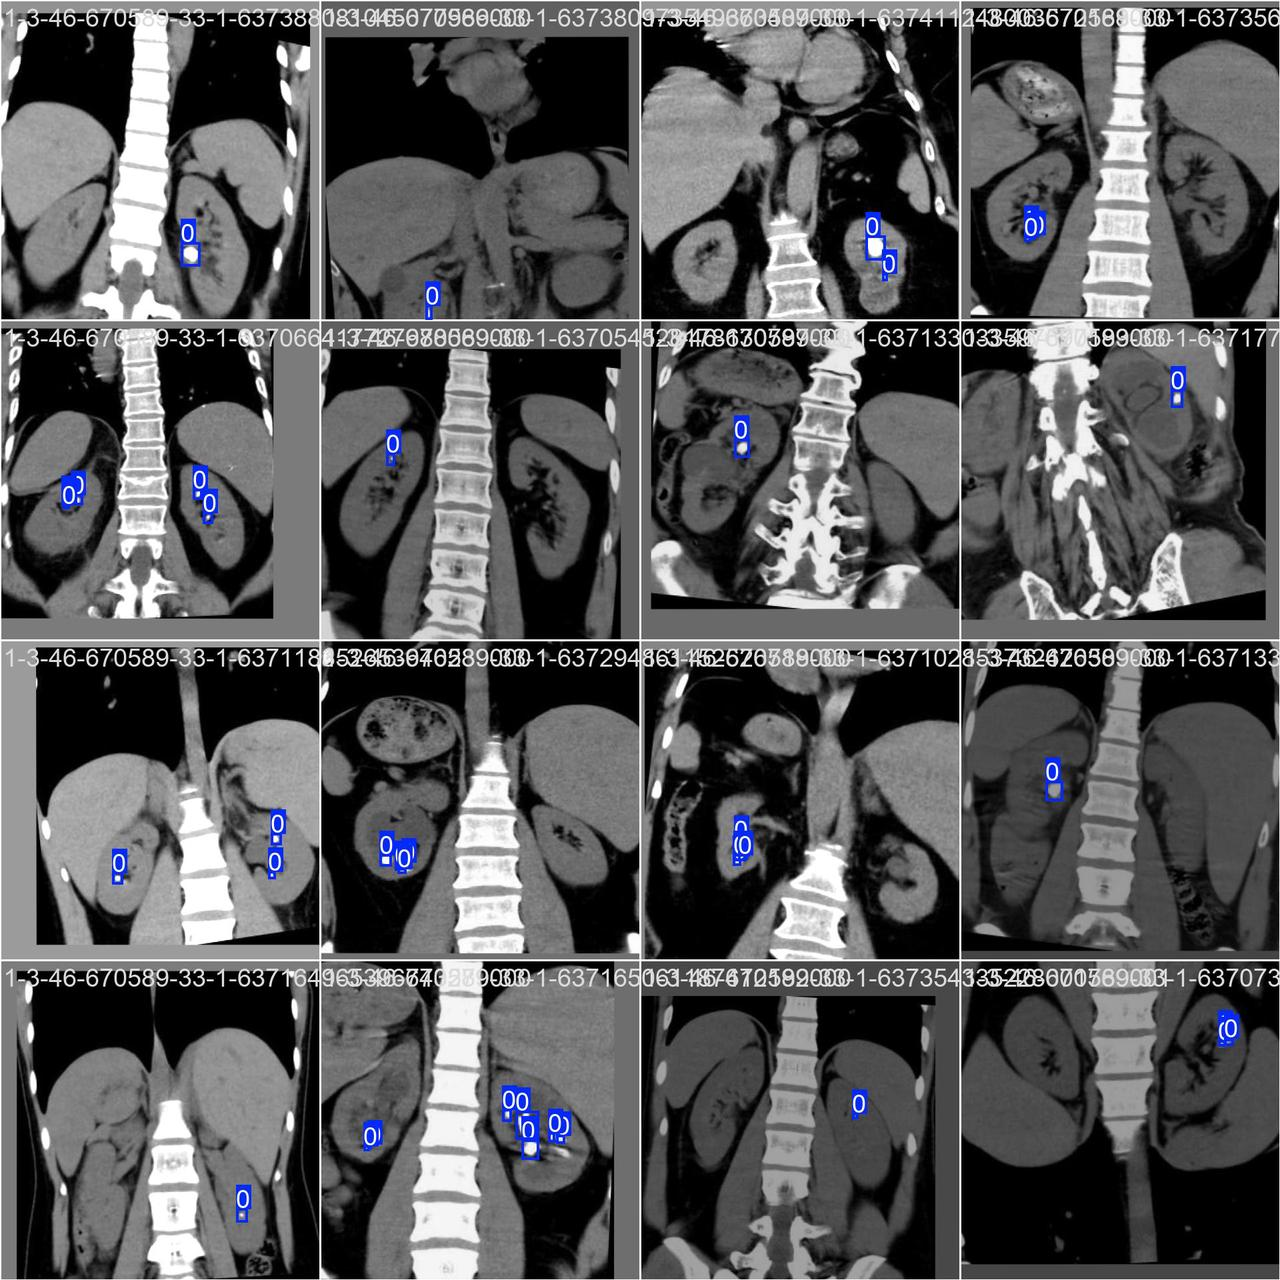

人工智能(AI)在医疗诊断领域的应用日益广泛,其中基于深度学习的肾结石检测成为一个备受关注的研究方向。通过利用计算机视觉和深度学习技术,我们可以自动识别肾脏影像中的结石病灶,精准判断结石的位置、数量等关键信息,提高肾结石的早期筛查效率与诊断精准度。本文将介绍基于深度学习的肾结石检测系统,并提供一个简单的Python代码实现,以便读者更好地了解这一技术。

肾结石是泌尿系统常见疾病,早期精准诊断对于避免病情进展、减少并发症至关重要。然而,肾结石在肾脏影像中可能表现为微小钙化点,且部分结石与肾脏周围组织密度相近、边界模糊,传统人工阅片易出现漏判、误判情况。若肾结石未能及时发现和诊断,可能引发肾积水、肾功能损伤、剧烈疼痛等并发症,严重影响患者生活质量与生命健康。因此,及早检测和准确识别肾结石情况,对于提升泌尿系统疾病诊断效率、保障患者治疗效果来说至关重要。

该数据集包含 1285张图片。